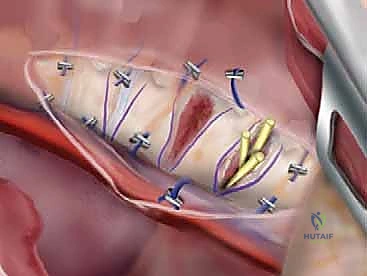

3. Sublaminar Wire Passage

This is the most perilous phase of the procedure. The ligamentum flavum is meticulously excised at the midline using Kerrison rongeurs to expose the epidural space. Doubled 16-gauge or 18-gauge stainless steel wires, pre-bent into a smooth, semi-circular loop, are carefully passed under each lamina.

The technique requires a delicate "flossing" motion. The tip of the wire must be kept in direct contact with the undersurface of the lamina at all times to avoid plunging into the spinal cord.

Once the loop emerges from the cephalad edge of the lamina, it is grasped with a nerve hook and pulled through. The wires are then sharply bent over the posterior elements to prevent them from slipping back into the canal and compressing the cord.